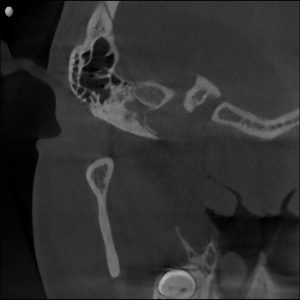

Radiographs confirmed it — his airway was constricted.

His jaw alignment had shifted to make breathing easier, but that adaptation had caused years of TMJ dysfunction.

Clinical & Radiographic Findings

- Forward head posture and low tongue position

- Narrow pharyngeal airway space

Radiographs confirmed increased airway space and balanced joint position.